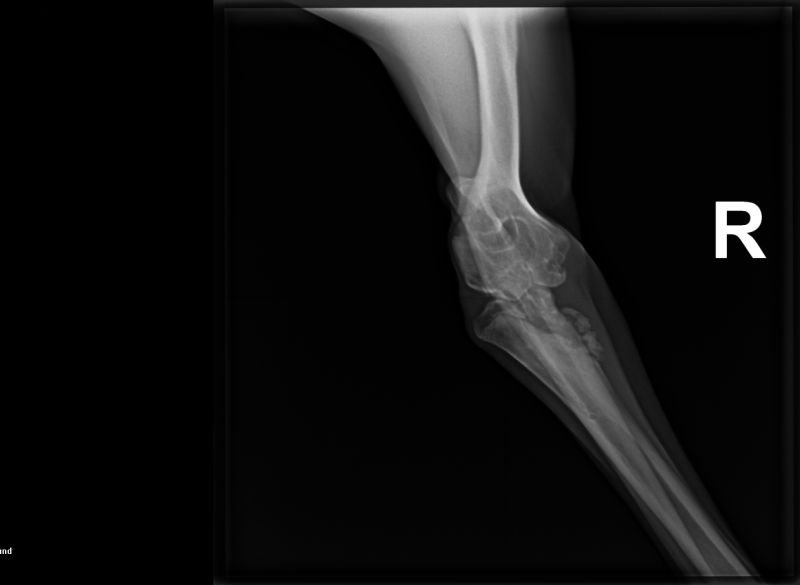

Nachdem sich nun fast 7 Monate gar Niemand für unseren Huckelberry interessierte, obwohl ihn sein angeknackstes Ellbogengelenk so gut wie gar nicht belastet, haben wir uns entschlossen, Huckelberry auf die "Paten -gesucht -Seite" zu verschieben.